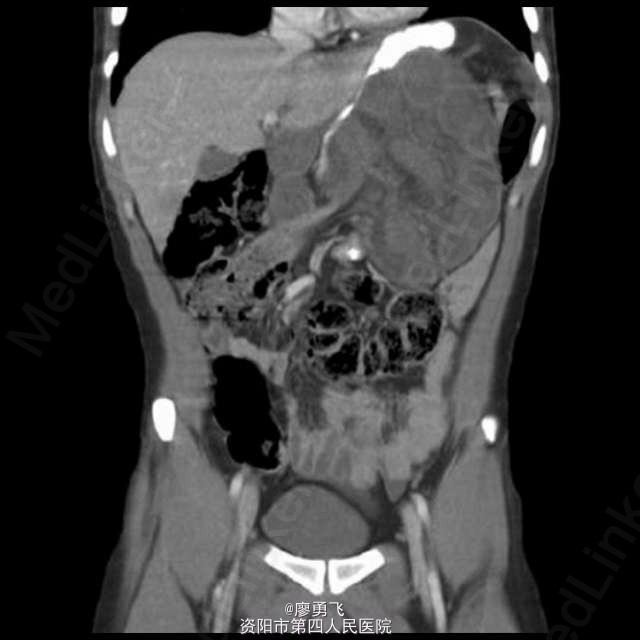

少见腹内疝——小网膜孔疝

青年男性,进食后突发上腹部疼痛,进行性加重,伴胆汁性呕吐,查体全腹部压痛,左上腹明显反跳痛。急诊剖腹探查证实过小网膜孔疝,暂无缺血坏死。术后恢复可。小网膜孔疝相对少见,及时诊断处理有助于避免肠缺血肠坏死等严重情况